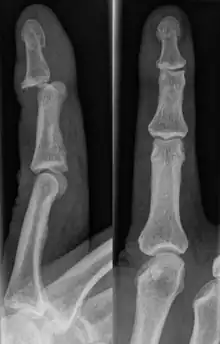

DIP Dislocation

PIP Dislocation

Dislocations can be categorised based on location and type. The finger can be split into three bones and two joints in an alternating order. From the fingertip to the knuckle, these are as follows; distal phalanx, distal inter-phalangeal (DIP) joint, middle phalanx, proximal inter-phalangeal (PIP) joint, and proximal phalanx. DIP dislocations are much less common than PIP dislocations,[2] due to the "stability provided by strong collateral ligaments, palmar plates, and tendinous insertions, as well as the short lever arm of the distal phalanx".[7] Dislocations can be categorised based on the direction that the fingertip moves in relation to the knuckle, be it in the direction of the palm (volar dislocation), or the direction of the back of the hand (dorsal dislocation). Of the two, dorsal dislocations are more common.[3] If reduction has been attempted, an x-ray of the dislocation should appear concentric if successful.[2] However, if there is a fracture present, there will be a misalignment of the joint, which will be evident from the radiograph.[2] Bach suggests a referral to a hand surgeon if a misalignment is present.[2]

Fractures are instances where the bone's structural integrity has been compromised. This is indicated by midshaft pain, as well as visual midshaft angulation or rotation.[3] As with any skeletal injury, an x-ray can be conducted to verify the presence of a fracture.[1] The distal phalanx is especially vulnerable to avulsion fractures, where a fragment of bone is ripped off when the tendon separates from the phalanx.[1] Avulsion fractures are especially common following a first time dislocation.[1] These are especially concerning, as it may indicate a complete tear of the extensor digitorum tendon. If left untreated, this may lead to permanent DIP extensor lag (inability to fully straighten the finger).[8]